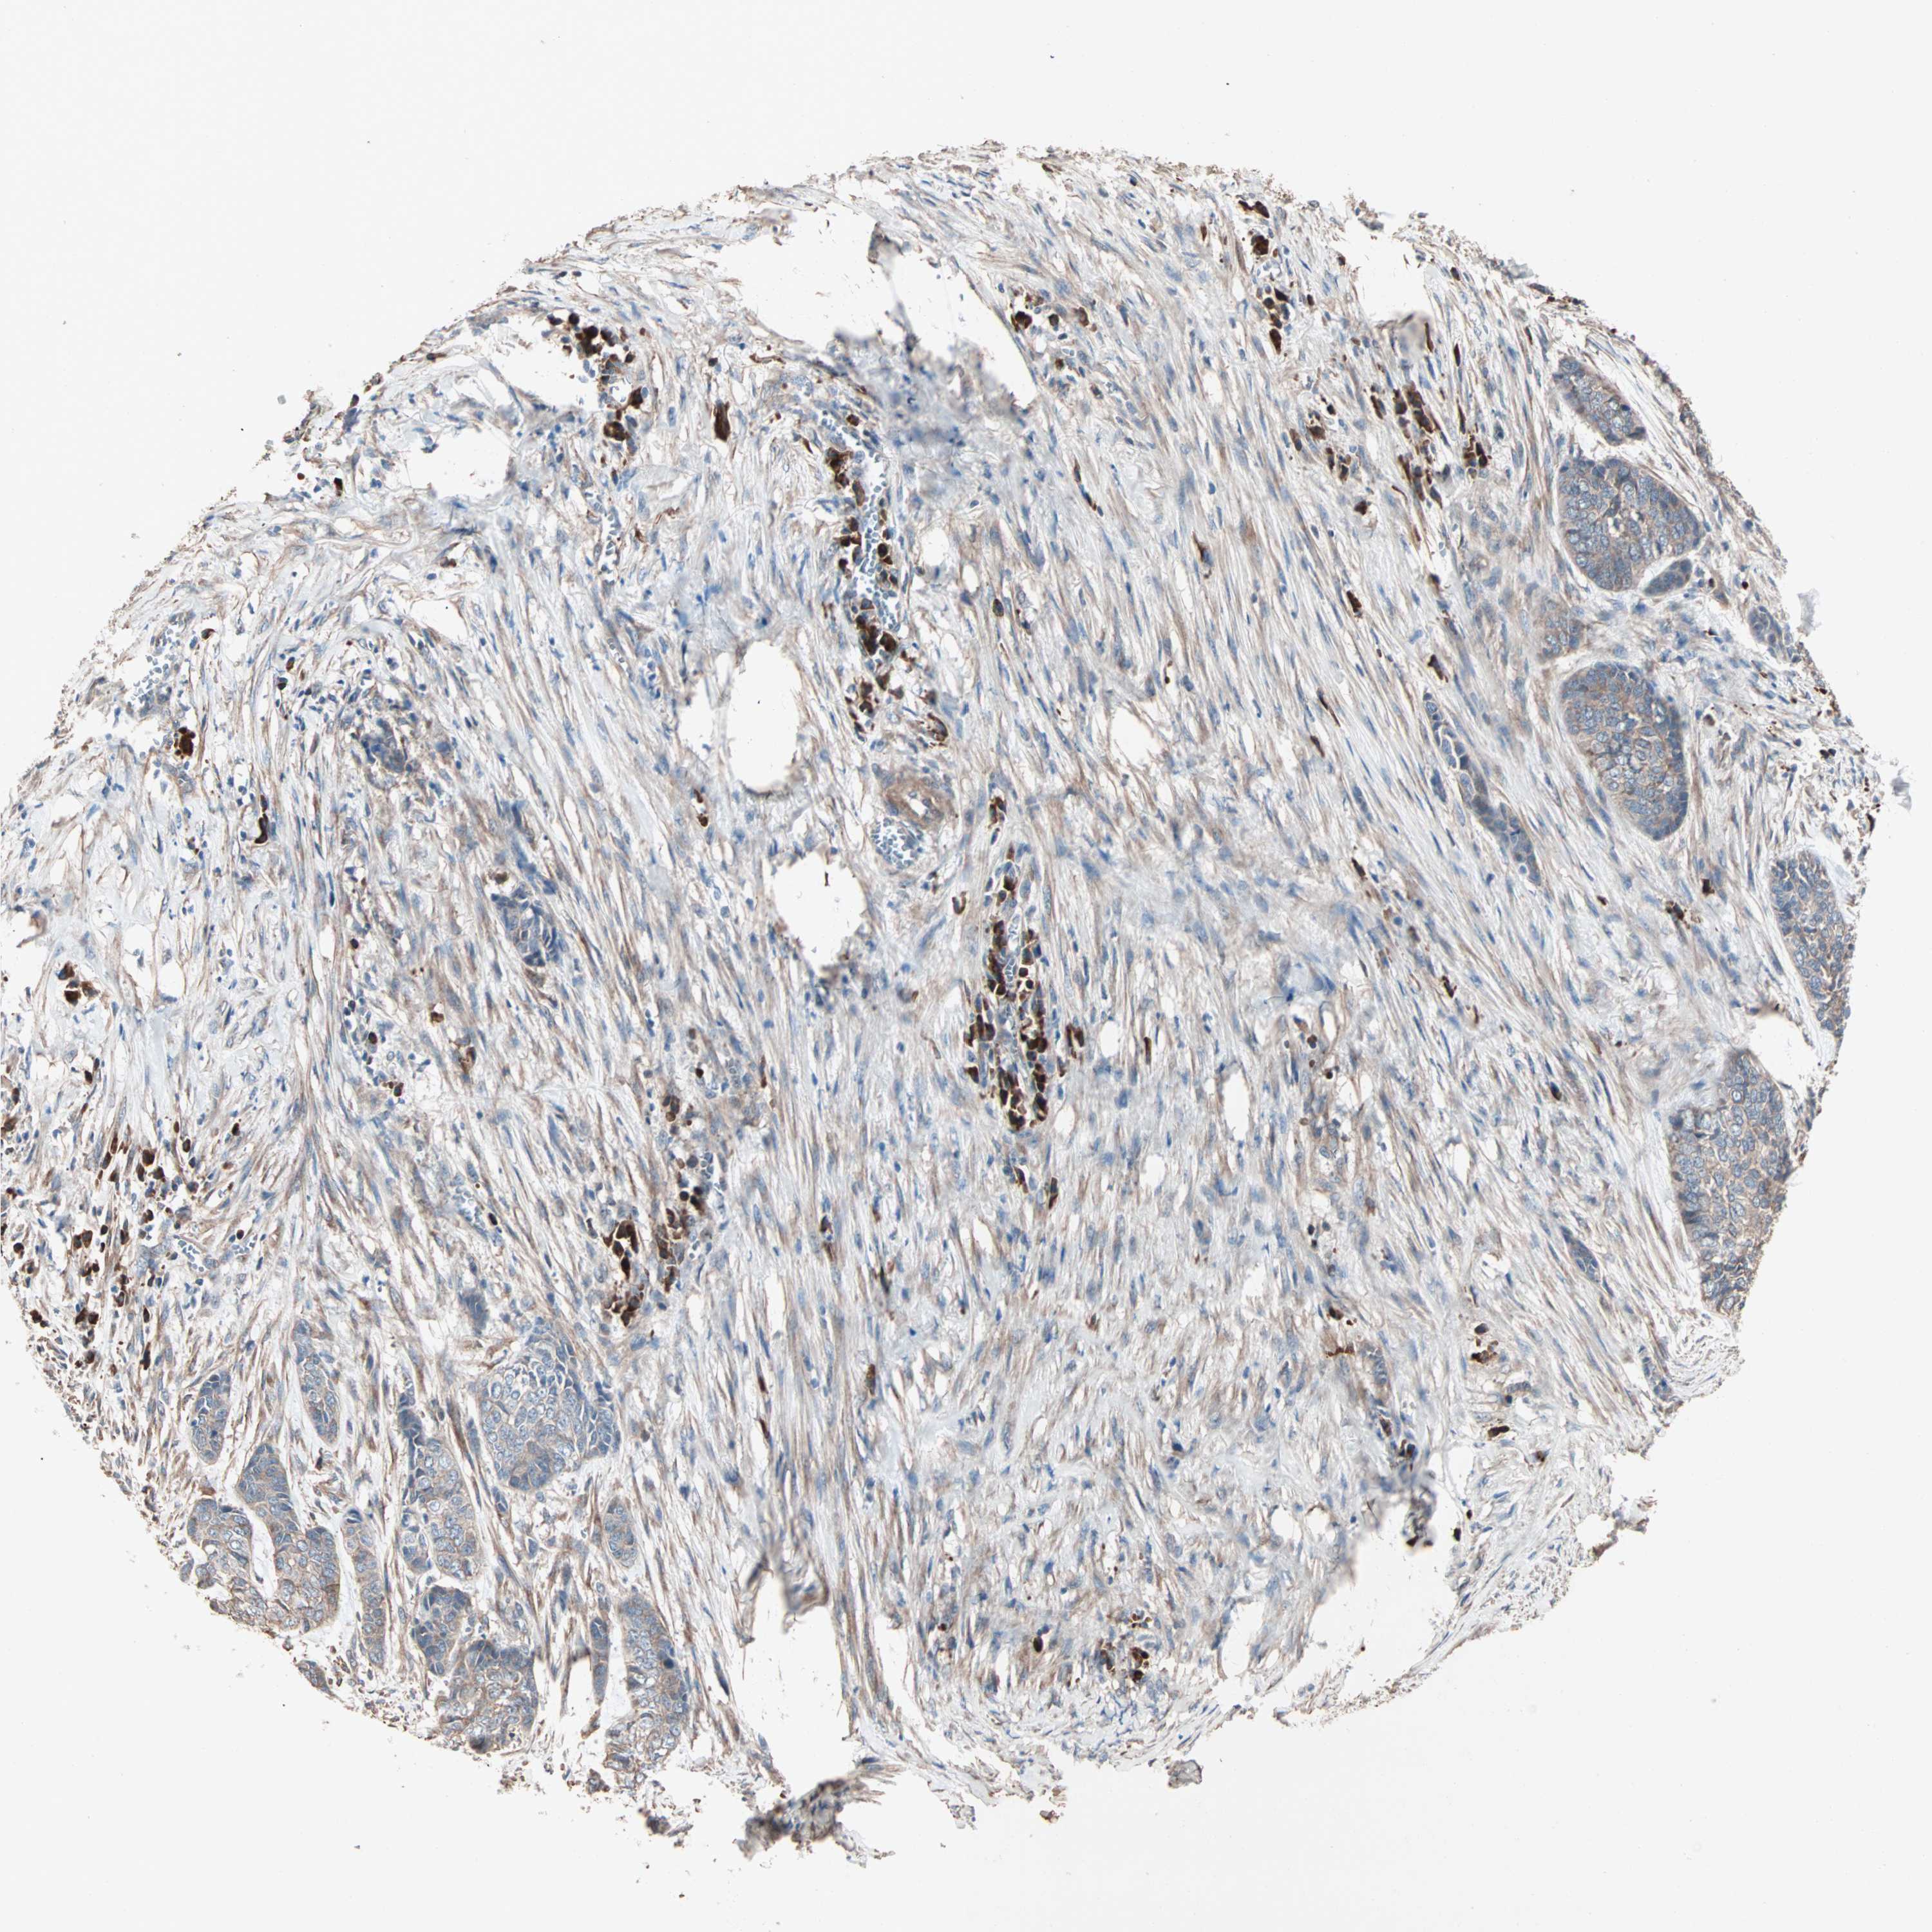

SKIN CANCER - Protein expressioni

A mouse-over function shows sample information and annotation data. Click on an image to view it in a full screen mode. Samples can be filtered based on level of antibody staining by selecting one or several of the following categories: high, medium, low and not detected. The assay and annotation is described here.

Each image is clickable and will lead to virtual microscopy that enables deeper exploration of all samples and also displays staining intensity scores, fraction scores and subcellular localization as well as patient and tissue information for each sample.

Antibody HPA007989

Staining

Medium

Moderate

>75%

Nuclear

Squamous cell carcinoma, metastatic, NOS